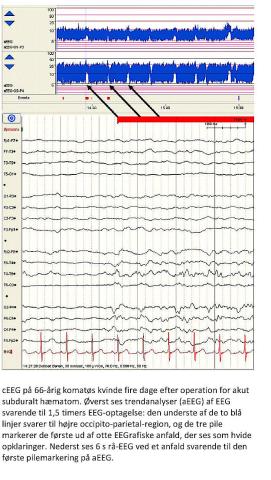

Mange patienter på intensivafdelinger har upåagtede nonkonvulsive epileptiske anfald (NKA). Dette kan påvises ved elektroencefalografi (EEG), men anfaldsaktiviteten er ofte intermitterende, og diagnosen kan da kun stilles ved langvarig EEG-overvågning, benævnt continuous EEG (cEEG). Afhængigt af typen af intensivafdeling har man ved cEEG fundet, at 8-48% af patienterne har NKA. Ofte findes vedvarende eller gentagne anfald svarende til en nonkonvulsiv status epilepticus (NKSE) [1]. NKSE optræder dels hos patienter, der ikke vågner op efter tilsyneladende velbehandlet konvulsivt anfald, dels er det en vigtig differentialdiagnose hos patienter med uafklaret koma (se figuren).